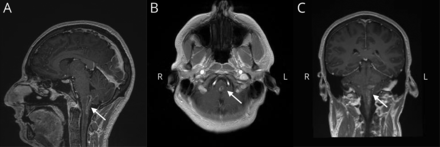

最初的头部CT是正常的。颈部CT对比显示左声带麻痹;耳朵、鼻子和喉咙声带评估确认完整的离开真的不动。腰椎穿刺最初显示460个有核细胞与淋巴细胞优势(79%),蛋白质68 mg / dL,葡萄糖72 mg / dL。meningitis-encephalitis PCR面板是负数,细菌和真菌的文化。核磁共振成像的大脑和颈椎有或没有对比显示一个扩大的,波形的,rim-enhancing病变在左背侧髓质扩展劣等C2-C3水平(图)。

(A)矢状多平面重建T1,梯度回波(MPR)显示波形的颈髓损伤扩展成绳(B)。轴向T1 post-contrast离开髓质(C)显示对比度增强。日冕MPR完成视觉3 d描述纵向病变。